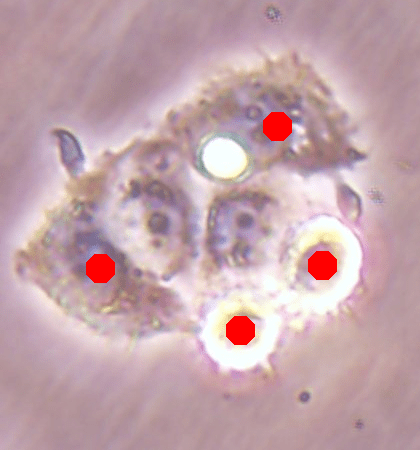

![]() |

| (a) | (b) |

| (c) | (d) |

For an example subimage given in Fig. 2a, these distance definitions are illustrated in Figs. 2b and 2c, respectively. The inner distance definition well indicates the cell centers since it uses the Euclidean distances from pixels to their closest cell centers. However, as it uses the centers as the reference point, the distance decrease from a center to its boundaries is the same for all directions and for all cells. Thus, when it is used alone, this definition imposes a circular and one-sized shape on the cells, as also seen in Fig. 2b. On the contrary, since the normalized outer distance is calculated with a reference to a cell boundary, this decrease may differ from one direction to another as well as from one cell to another, depending on the shape and size of the cell. Thus, it better preserves the morphological characteristics of cells, as seen in Fig. 2c.

The proposed DeepDistance model considers cell detection as a multi-task regression problem that estimates two distance maps from the RGB image, one for formulating the main task of cell detection and the other as an auxiliary task with the motivation of more effectively learning the main task. The FCN architecture given in the previous section is designed to learn these two regression tasks at the same time. This section discusses how this model can be extended to cover more auxiliary tasks, concurrent learning of which may further increase the performance of the main task. For this purpose, this section implements an extended version of the DeepDistance model that comprises an additional task of cell pixel classification. This additional task aims to construct a classification map (as shown in Fig. 2d) from the shared features of the encoder path111To take overlapping cells apart, and hence to obtain an improved map, cell boundaries are widen and subtracted from the classification map. This improved map is also used in the comparison methods to make fair comparisons.. Note that here, instead of defining another regression problem as the additional task, we use a classification problem in order to demonstrate that the model can easily be extended to cover the auxiliary tasks related with regression as well as classification.